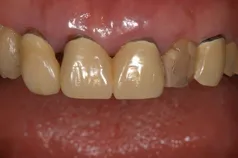

[症例1]

重度の歯周病で奥歯がすでになくなっており、そのため前歯もグラグラの状態でした。

右上の前歯(向かって左上)は自然に抜け落ちたそうです。

下の前歯の裏側には多量の歯石がたまっています。

【処置内容】

歯周初期治療、全体に歯周外科処置を実施、その後セラミックブリッジ、セラミッククラウン、

右上6・5番、左上3・4・5・6番、左下6番、右下4・6番にインプラントを実施。

• 治療期間:約2年

• 治療費:400万円

• 治療回数:30回